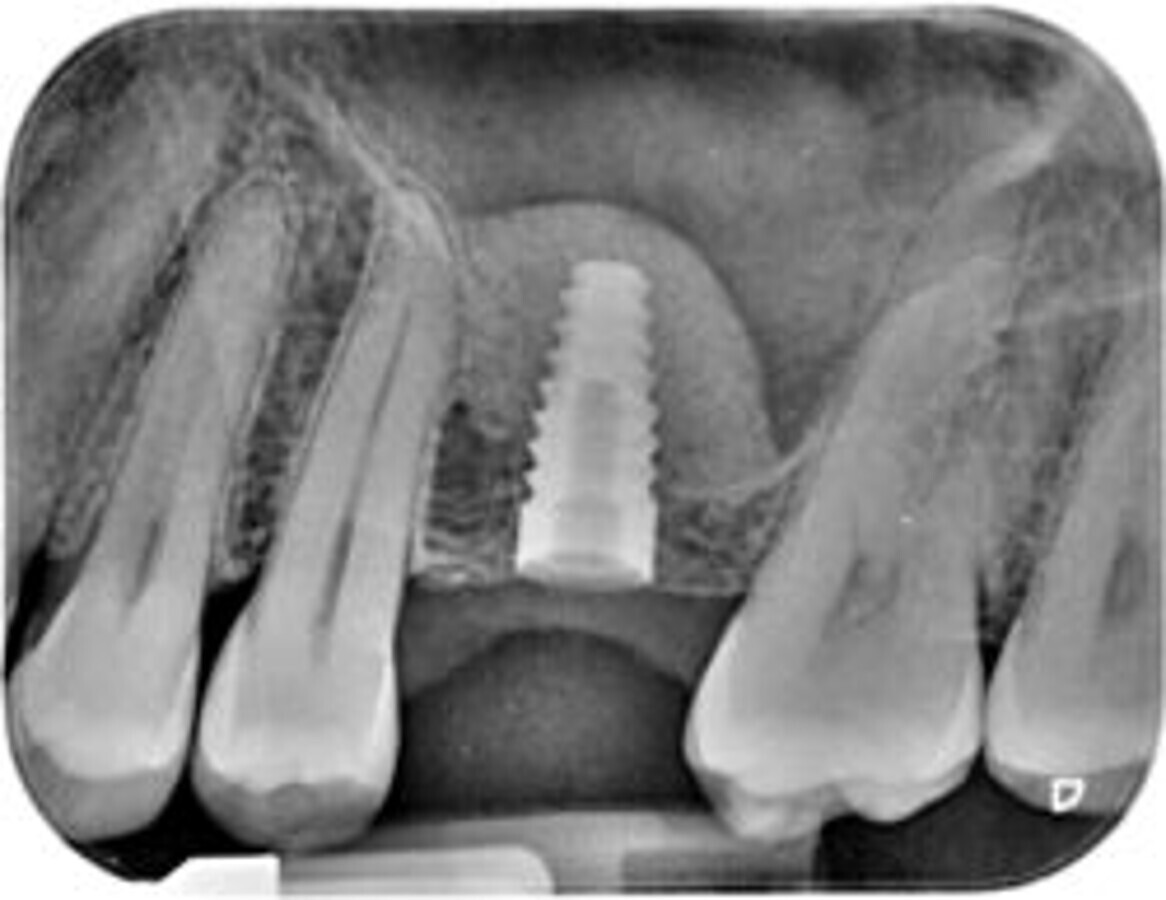

If there is one key to success in the esthetic zone, it is the ‘3-D implant positioning’. Most errors in the aesthetic zone occur due to malposed implants. Hence my advice for youngsters is, irrespective of what surgical procedure is being executed, like post-extraction immediate placement, socket shield procedure, ridge-split procedure, ridge expansion of conventional placement, the ideal prosthetically-driven implant placement is sacrosanct.